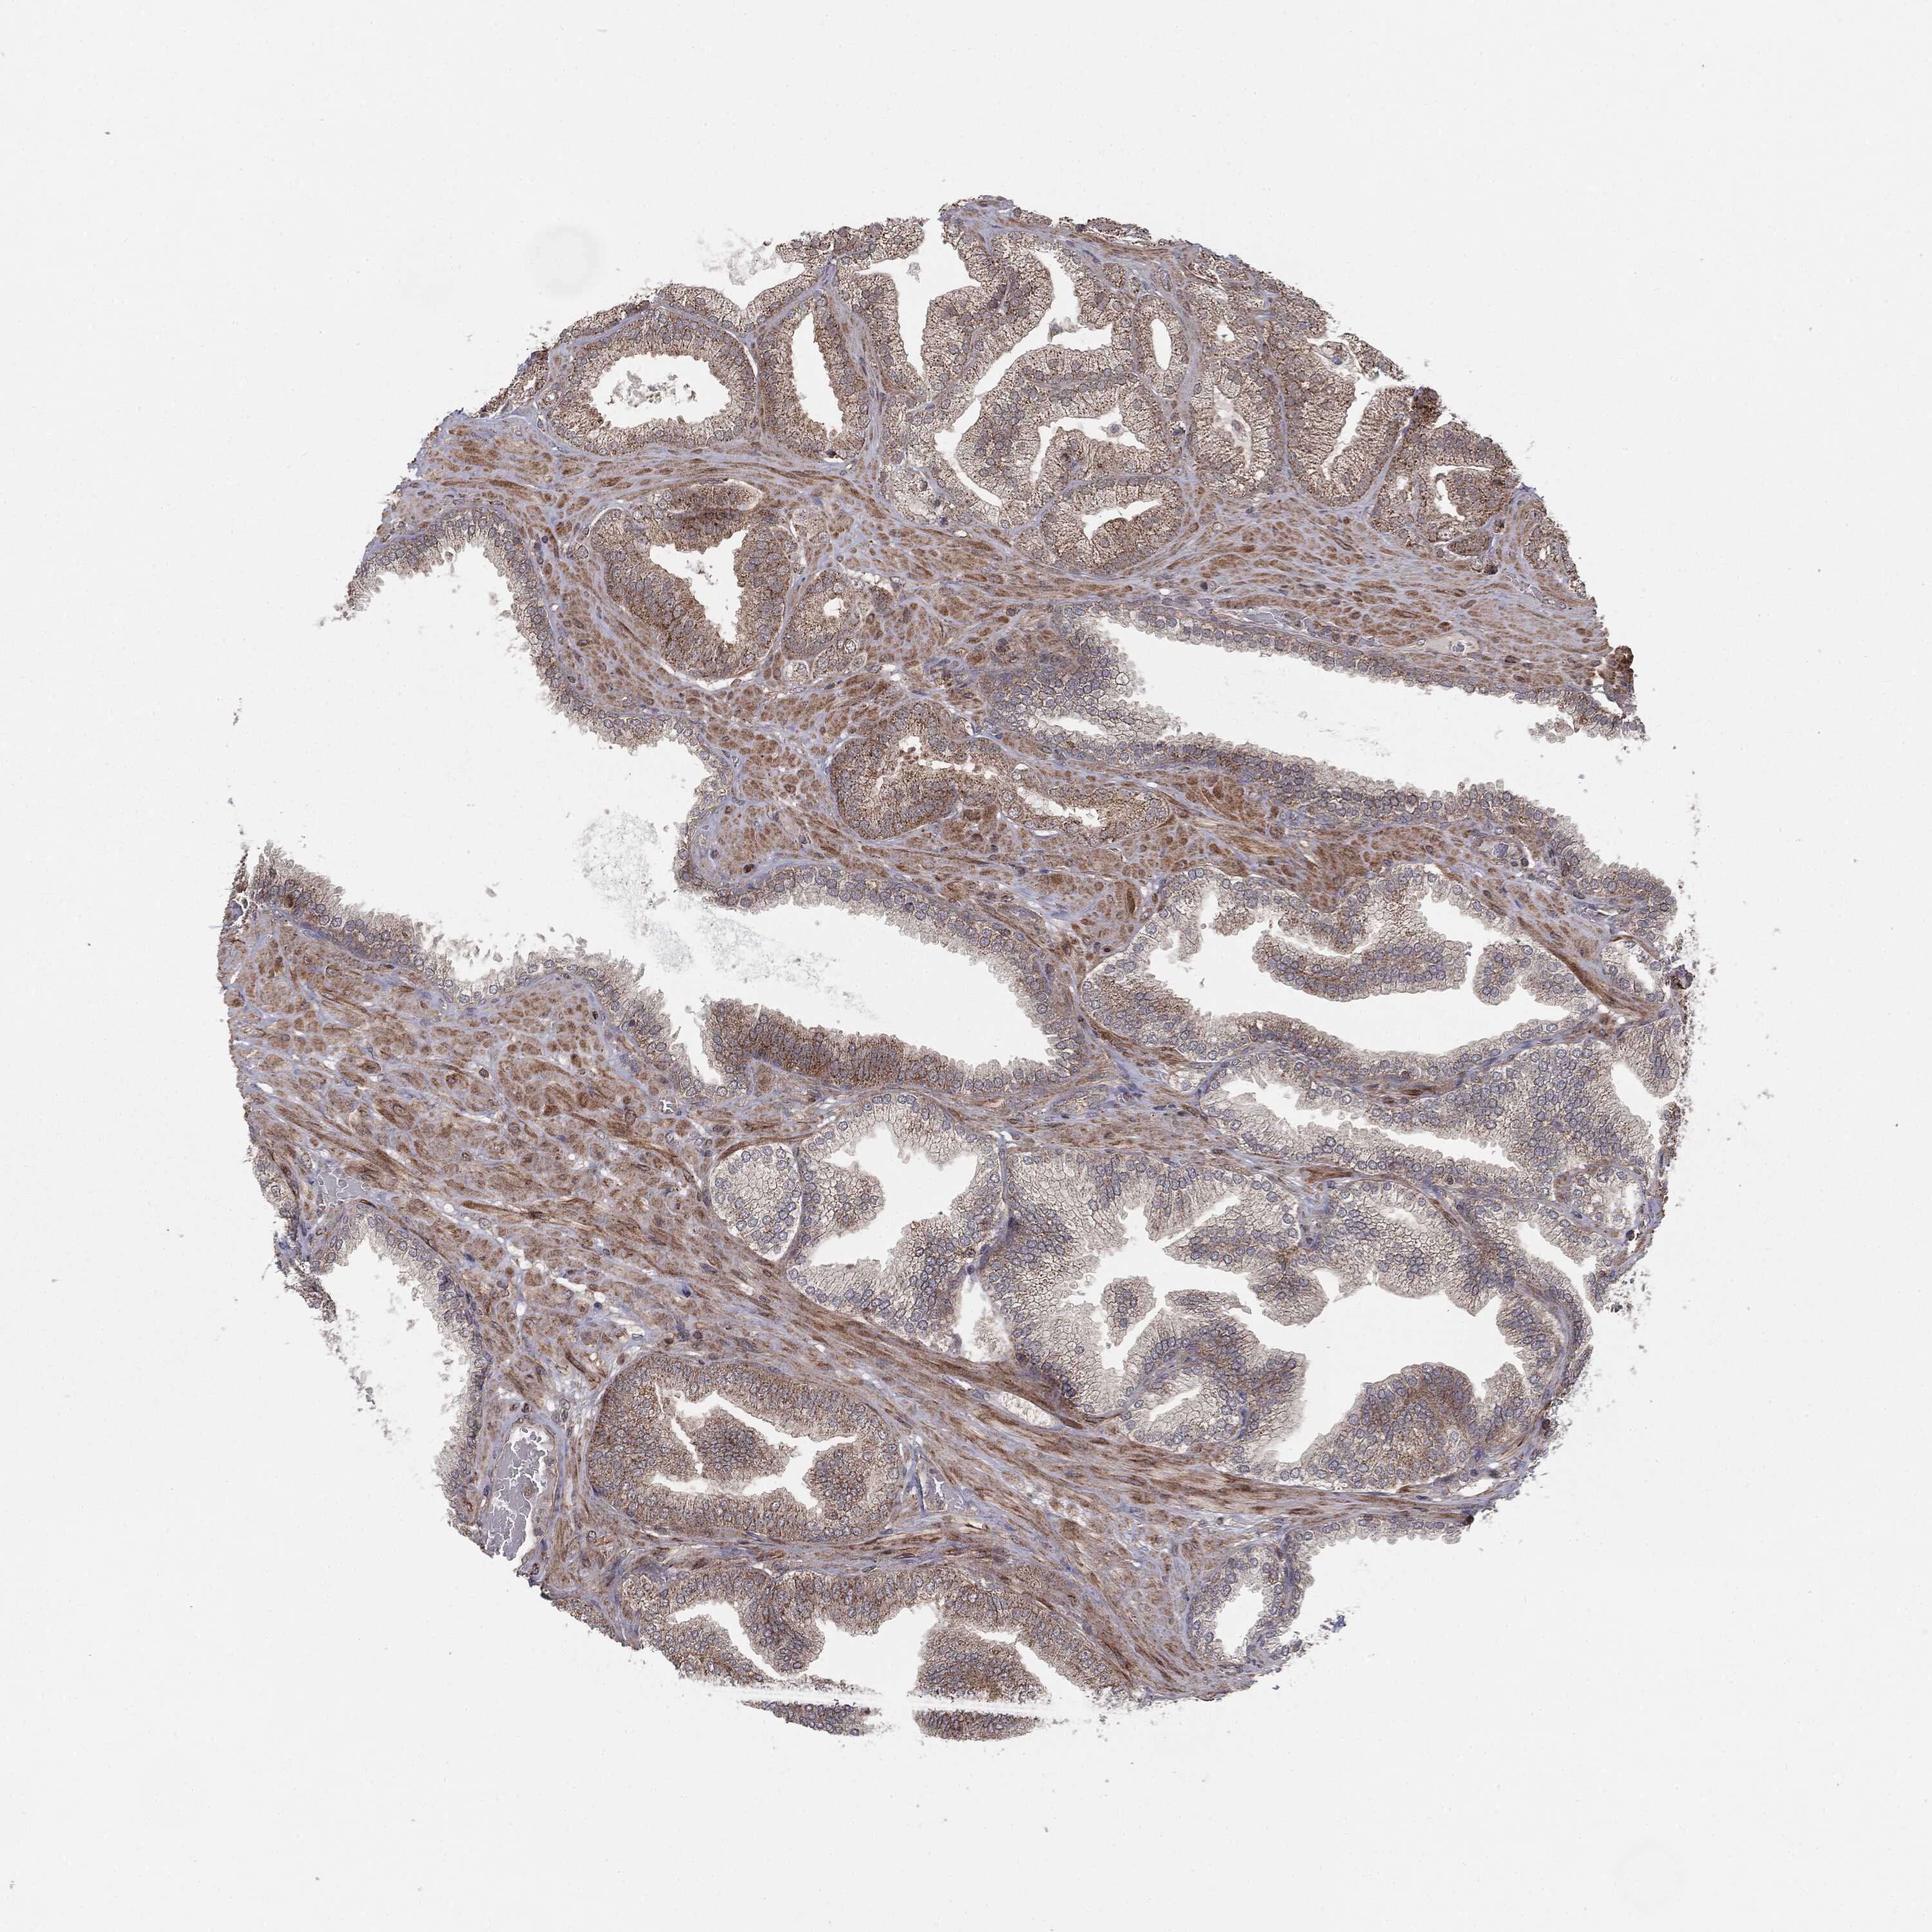

PROSTATE CANCER - Protein expressioni

A mouse-over function shows sample information and annotation data. Click on an image to view it in a full screen mode. Samples can be filtered based on level of antibody staining by selecting one or several of the following categories: high, medium, low and not detected. The assay and annotation is described here.

Note that samples used for immunohistochemistry by the Human Protein Atlas do not correspond to samples in the TCGA dataset.

Antibody stainingi

Antibody staining in the annotated cell types in the current human tissue is reported as not detected, low, medium, or high, based on conventional immunohistochemistry profiling in selected tissues. This score is based on the combination of the staining intensity and fraction of stained cells.

Each image is clickable and will lead to virtual microscopy that enables deeper exploration of all samples and also displays staining intensity scores, fraction scores and subcellular localization as well as patient and tissue information for each sample.

CAB069425

CAB080053

CAB080065

CAB080070

CAB080081

CAB080095

CAB080097

Staining

High

Medium

Low

Not detected

Intensity

Strong

Moderate

Weak

Negative

Quantity

>75%

75%-25%

<25%

None

Location

Nuclear

Cytoplasmic/membranous

Cytoplasmic/membranous,nuclear

Adenocarcinoma, High grade

Adenocarcinoma, NOS

Adenocarcinoma, Low grade